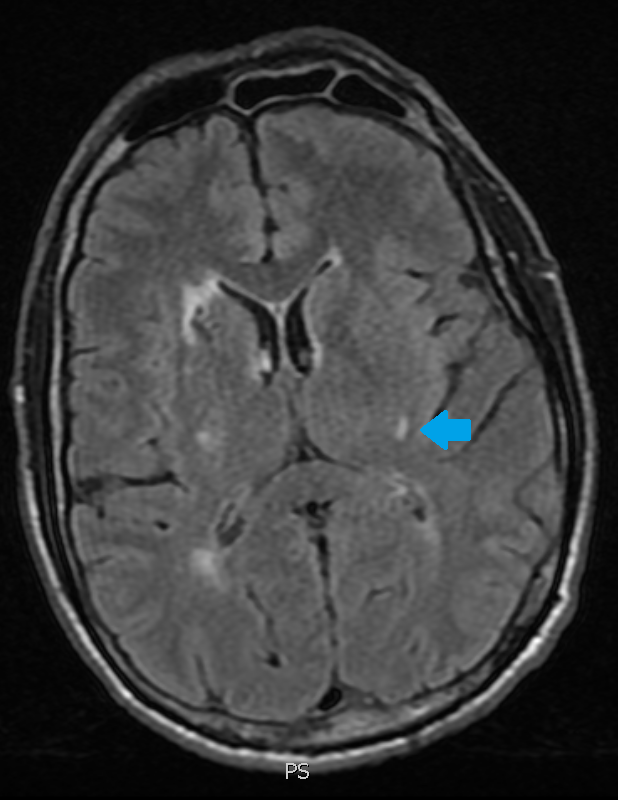

Scroll through the T2 FLAIR images in the slideshow below to follow a left basal ganglia injury with Wallerian degeneration of the descending motor axons in the brain stem.

The original injury was the small lesion on the first slide. The white matter abnormality pointed out on the subsequent slides is from Wallerian axonal degeneration.